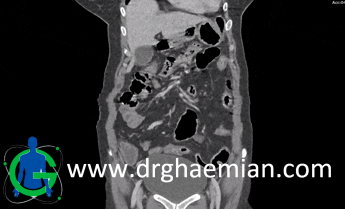

سی تی اسکن شکم و لگن یکی از روش های تصویربرداری با سی تی اسکن است. این روش با استفاده از اشعه ایکس تصاویر عرضی از ناحیه شکمی و لگنی ایجاد میکند. در این کیس کلیههای متقاطع و جوشخورده دیده میشود.

در سی تی اسکن اسپیرال شکم و لگن با کنتراست خوراکی (Neutral) و با و بدون کنتراست وریدی (مولتی دیدکتور 16 با مقاطع ظریف و بازسازی های ساژیتال و کرونال):

کلیه چپ در محل آناتومیک خود رویت نمی شود و به صورت اکتوپیک به پل تحتانی کلیه راست متصل می باشد که مطرح کننده

آنومالی Ectopic crossed fused kidneys می باشد.

آنژیومیولیپوم 8mm در پل فوقانی کلیه راست و کیست 10mm در پل فوقانی این کلیه مشهودند.